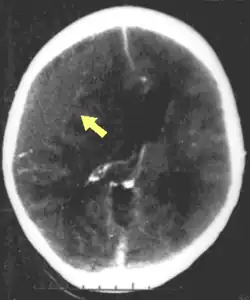

![]() | |

| CT scan showing cerebral contusions, hemorrhage within the hemispheres, and subdural hematoma. There is also displaced skull fracture of left transverse parietal and temporal bones.[2] | |

One type of focal injury, cerebral laceration, occurs when the tissue is cut or torn.[37] Such tearing is common in orbitofrontal cortex in particular, because of bony protrusions on the interior skull ridge above the eyes.[31] In a similar injury, cerebral contusion (bruising of brain tissue), blood is mixed among tissue.[23] In contrast, intracranial hemorrhage involves bleeding that is not mixed with tissue.[37]

Hematomas, also focal lesions, are collections of blood in or around the brain that can result from hemorrhage.[11] Intracerebral hemorrhage, with bleeding in the brain tissue itself, is an intra-axial lesion. Extra-axial lesions include epidural hematoma, subdural hematoma, subarachnoid hemorrhage, and intraventricular hemorrhage.[38] Epidural hematoma involves bleeding into the area between the skull and the dura mater, the outermost of the three membranes surrounding the brain.[11] In subdural hematoma, bleeding occurs between the dura and the arachnoid mater.[23] Subarachnoid hemorrhage involves bleeding into the space between the arachnoid membrane and the pia mater.[23] Intraventricular hemorrhage occurs when there is bleeding in the ventricles.[38]